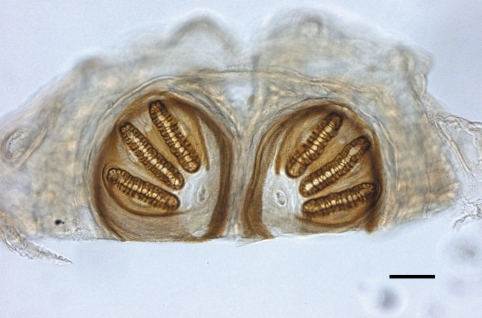

On 1 July 2009, 4 days after hospitalization, 5 fly larvae were discovered moving inside her nose (

Fig. 1). They were removed endoscopically, and sent to the parasitology laboratory for analysis. Examination of the patient's nose revealed no significant pathologic changes. The larvae were white and 10.8 ± 2.6 mm × 2.0 ± 0.7 mm in size. Examination of posterior spiracles on a glass slide under light microscopy showed that they were in the family Calliphoridae, probably

Lucilia sp., which is endemic in Korea (

Fig. 2). They were fixed in 10% formalin and used for identification. They were identified by Lee In-Yong in Department of Environmental Medical Biology, Yonsei University College of Medicine, as the third instar larvae of

Lucilia sericata. By additional endoscopic examination, no larvae were found from her. She returned from the comatose state, and did not complain any clinical signs of myiasis.

Fig. 1The larvae of Lucilia sericata isolated from the patient's nose. One larva was omitted because it was used for sectional views. A scale is corresponded to 1 mm.

Fig. 2Posterior spiracles of a third-tage larva of Lucilia sericata sampled in the nose of the patient. Bar = 100 µm.